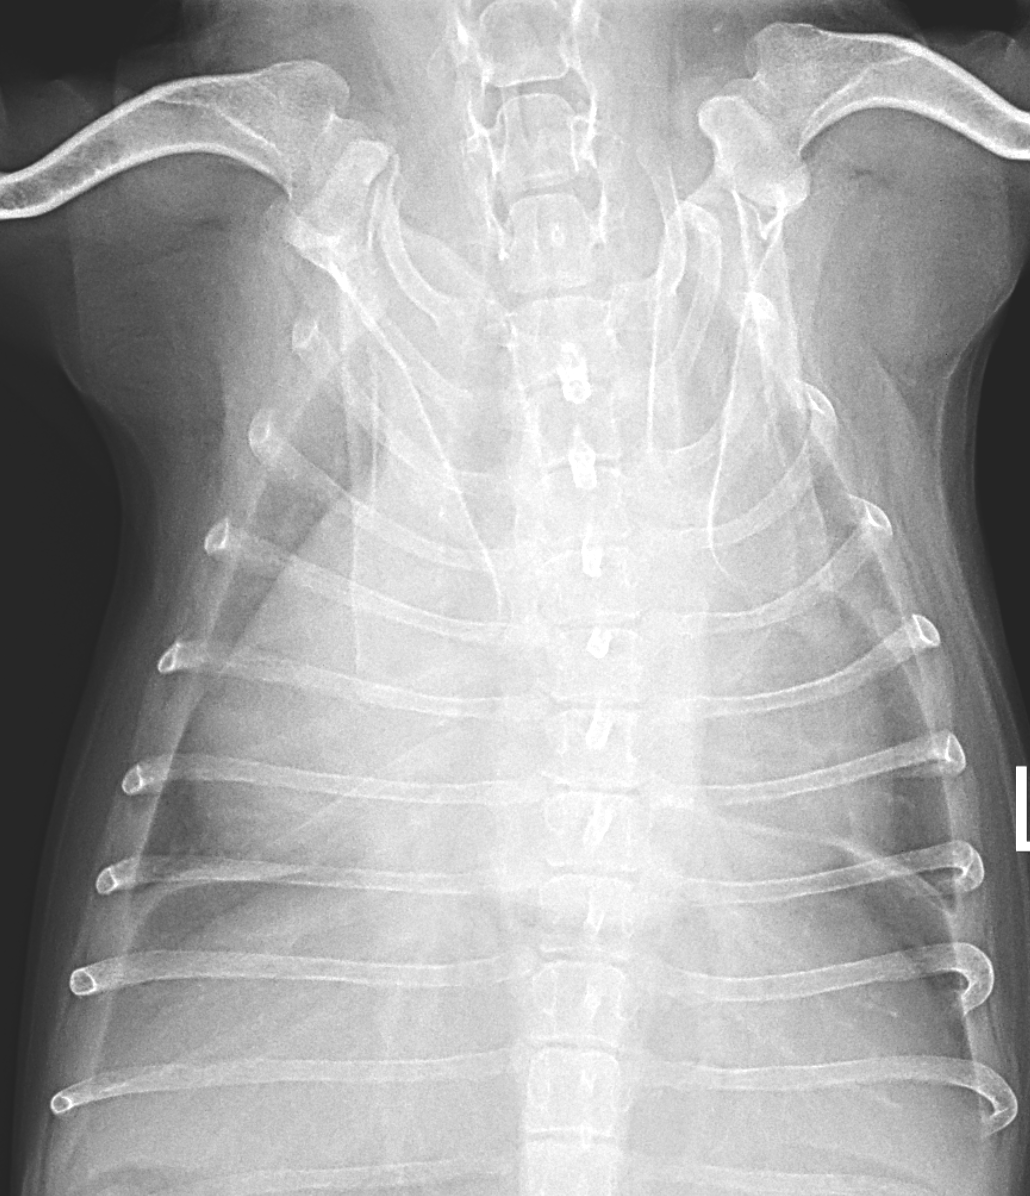

右心不全による胸水貯留

高齢の小型犬が、呼吸困難を主訴に紹介されました。

胸水と腹水の貯留により呼吸が苦しくなっていましたが、これらは心不全が原因となって起きている症状です。